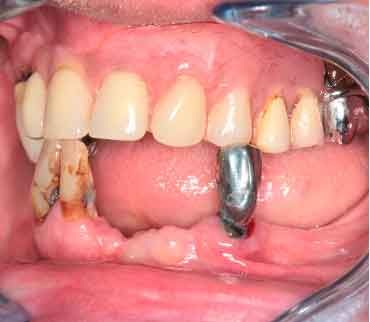

66 years old patient. Wishes to regain functional comfort and improve aesthetics.

Complaints :

- Lack of stability of his removable prosthetics

- Difficulties in eating

- Sagging of the upper lip

The periodontal structures of the remaining teeth are no longer sufficient. An edentulism is considered. The treatment plan is directed towards a removable maxillary complete prosthesis and an implant-supported mandibular complete prosthesis.

Picture - Initial bite situation